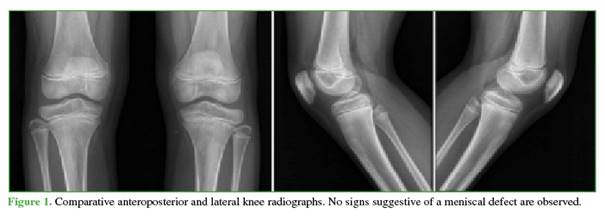

He was referred to an orthopedic subspecialist. Physical examination revealed tenderness on palpation of the medial joint line, painful flexion-extension with full range of motion (0-130°), and a positive medial McMurray test; the remainder of the exam was normal. Given these findings, an MRI of the left knee was requested (Figure 2). Imaging showed an enlarged medial meniscus (incomplete) without displacement, with intrameniscal degeneration.